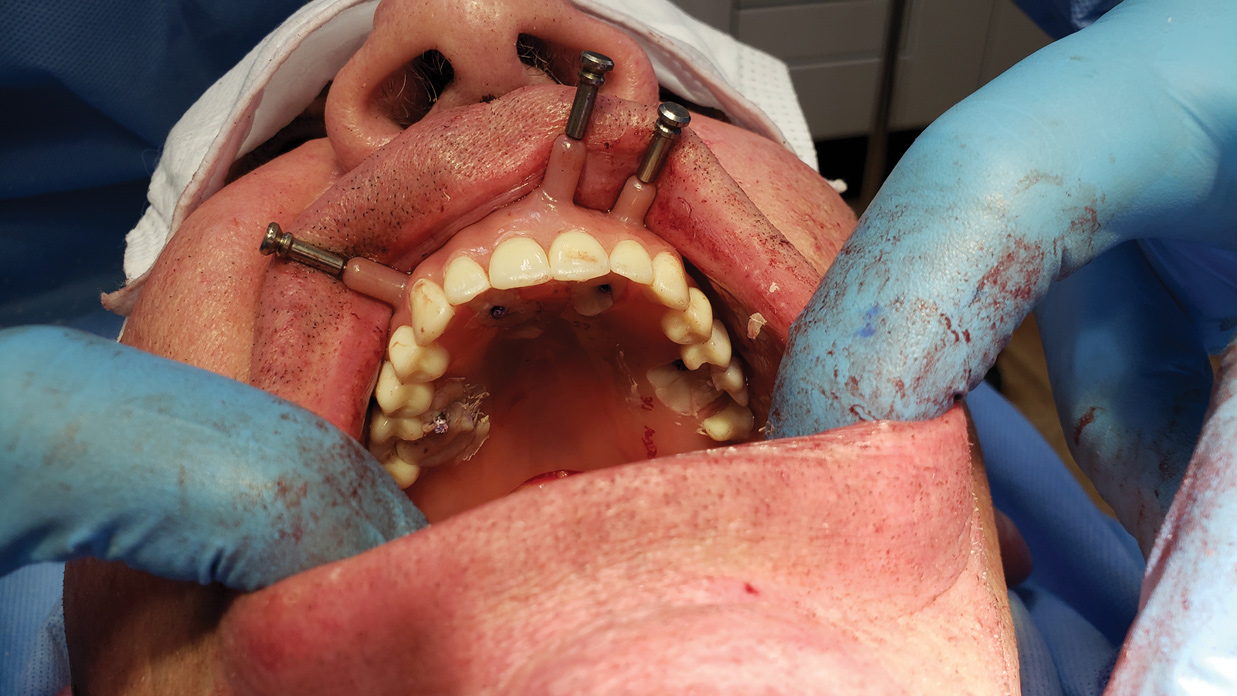

Figure 8: Dental implant is ready for installation with dynamic navigation in the mandible.

Figure 8

Figure 9: Titanium temporary cylinders that will become part of the conversion prosthesis are placed on transmucosal abutments.

Figure 9